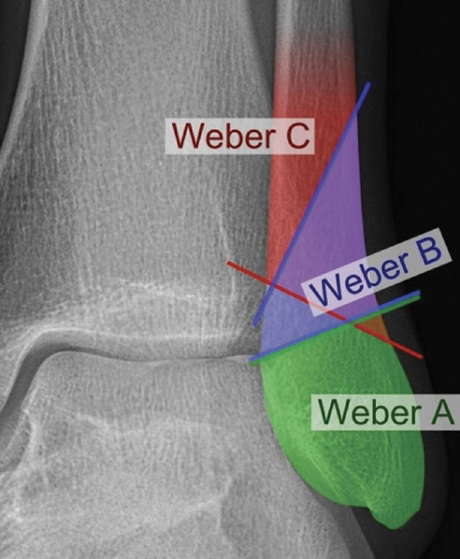

@MoAImam radiopaedia.org/articles/weber…

Respectfully disagree. All the lines of force/fracture go through the joint line. My understanding is the same as that demonstrated by the above website.